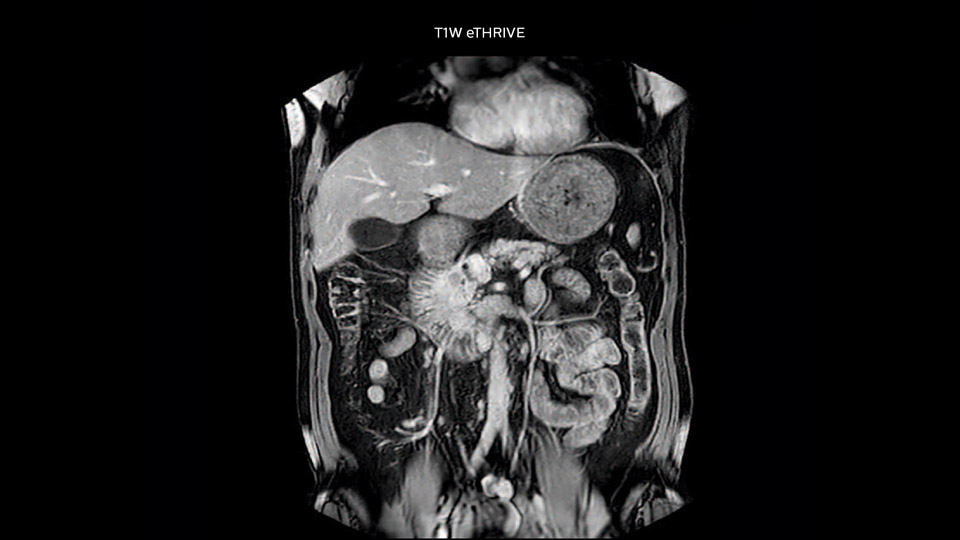

Comparison of liver MRI with and without MultiVane XD motion correction

In this example the image quality of the MultiVane XD images is evidently better than in the images without MultiVane XD. Ingenia 1.5T with dS Torso coil solution.

“We acquire one transversal high resolution T2-weighted sequence with 3 mm slice thickness, for example for pancreas or liver lesions. Then we also add a T2 fat suppressed MultiVane XD SPIR sequence. We perform these two routinely in our liver imaging. We use high dS SENSE factors to significantly shorten scan times to 2-4 minutes, which can improve our protocol; it’s a very robust scan.”

“We include mDIXON for the dynamic sequences because of the robust and homogeneous fat suppression we get with that. We had been using eTHRIVE, but we are now quite happy with mDIXON. Sometimes we use a medication to calm the bowels, to further improve the image quality.”